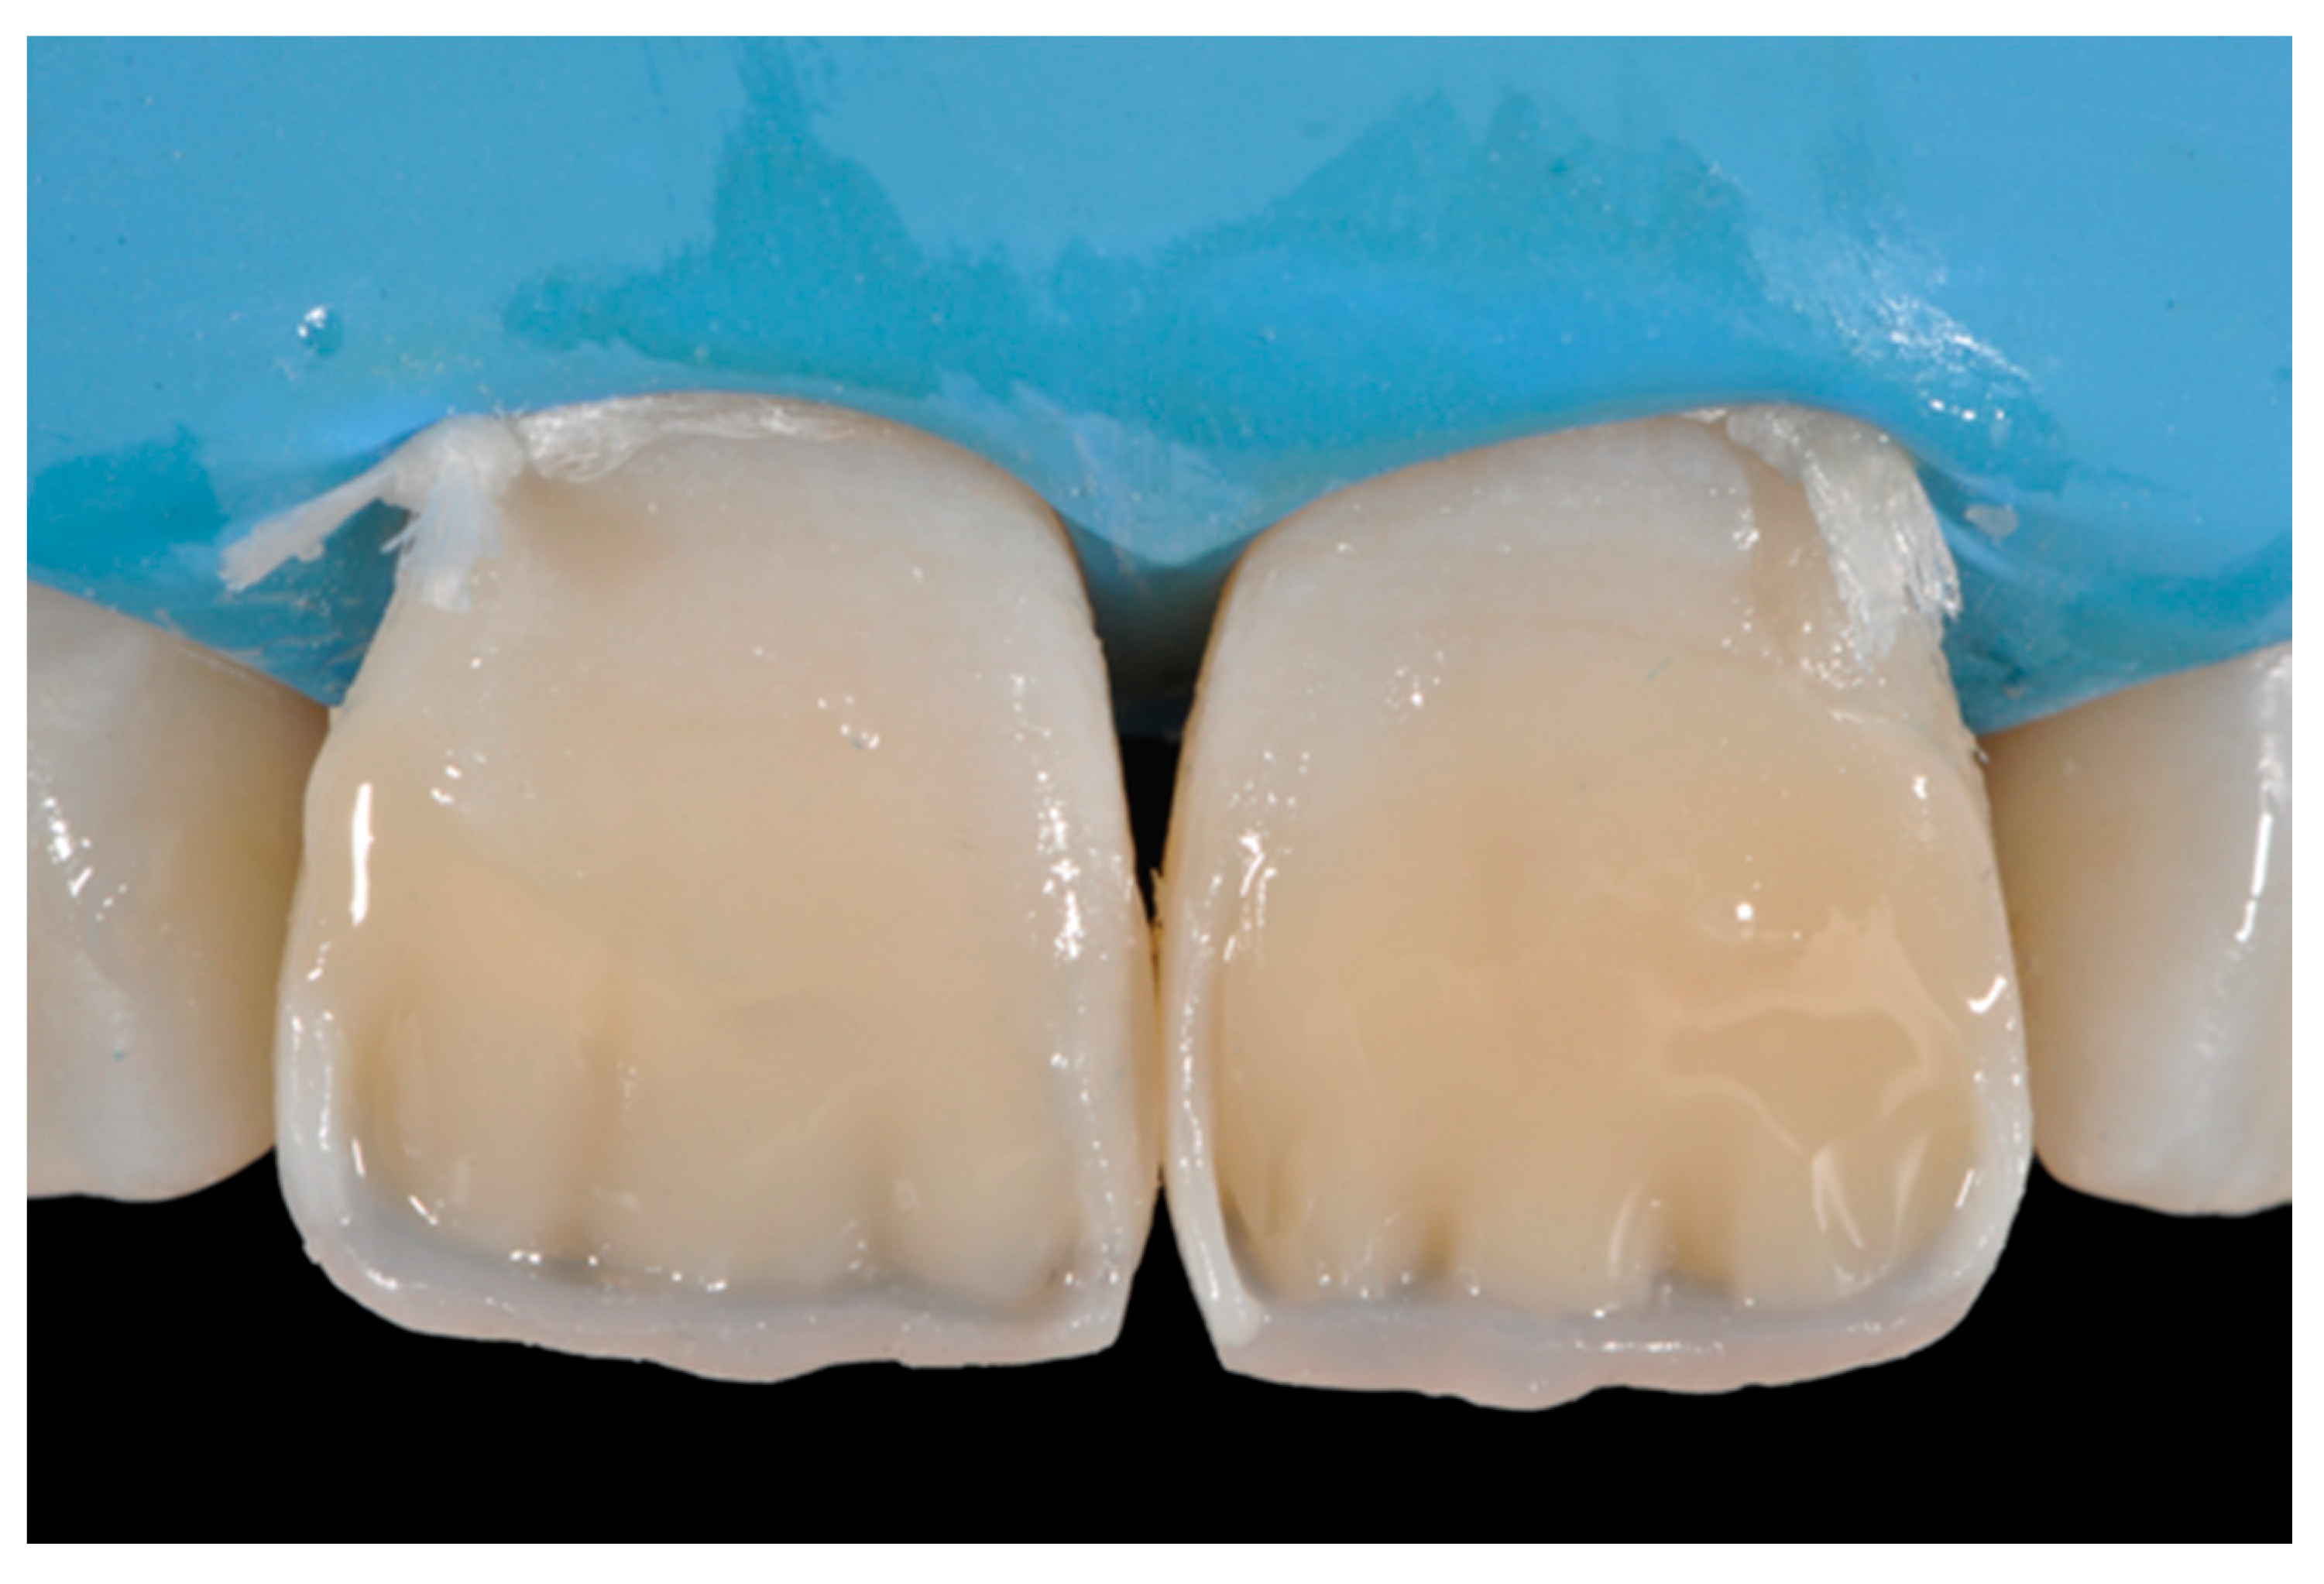

2.1.3. Completion of the Layering Procedure, Finishing and Polishing

A single shade of dentin (Clearfil Majesty ES-2, A1D, Kuraray Noritake Dental, Tokyo, Japan) was then applied placing separate increments (Figure 10 and Figure 11) to build the dentinal body, leaving space for incisal translucencies. The translucent shade (Clearfil Majesty ES-2, A1E, Kuraray Noritake Dental, Tokyo, Japan) was then applied to complete the restoration (Figure 12).

Figure 12.

Enamel layer applied. Reprinted from Restauri diretti nei settori anteriori, G. Paolone, S. Scolavino, © 2021, with permission from Quintessence Publishing Italy.